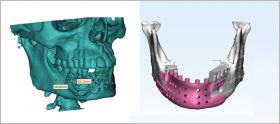

3D Incredible Medical is the only metal 3d printing company in India. We use the latest Metal 3D printing (Additive Manufacturing) manufacturing technology. With this latest manufacturing process, the parts are built very close to the required dimensions with an accuracy of 0.2 mm. 3D Incredibles Medical specializes in manufacturing various Maxillofacial Designs, ortho implants solutions , Anatomy Model, and many more.

Maxillofacial Designs By 3D Incredible for Maxillofacial Prosthetics